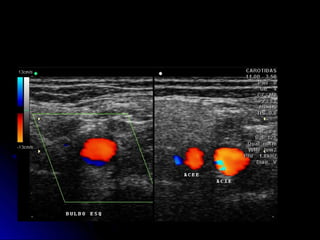

DocumentaçãoDocumentação

ACC, Bifurcação e BulboACC, Bifurcação e Bulbo

Modo B e ColorModo B e Color

ACC, ACI e ACEACC, ACI e ACE